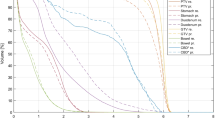

Target Coverage

There was no overall differences seen in the PTVD95 or PTV EUD (-20) between the simple and index IMRT plans (mean 44.6 Gy vs. 44.5 Gy, p = 0.066). As expected, the dose to 0.5 cc of the PTV was statistically less for simple IMRT compared to index IMRT (mean 39.5 Gy vs. 40.0 Gy, p0.006), as was PTVD99 (mean 40.6 Gy vs. 41 Gy, p < 0.001) (figure 2), since small differences in minimum dose to 0.5 cc of PTV were permitted in the study design and likely of little clinical significance as summarized in table 3. The maximum doses within PTV were higher for the simple IMRT compared to index IMRT (mean 123.4% vs. 121.3%, p = 0.036).

Maximum dose delivered to the heart (mean 25.3 Gy vs. 24.5 Gy, p = 0.048) and ribs (mean 38.7 Gy vs. 37.7 Gy, p = 0.044) was significantly higher for simple IMRT (figure 3) but no other statistically significant differences were seen in other OARs, liver Veff, biological liver NTCP or mean liver dose. Examples of simple IMRT and index IMRT plans are shown in figure 4.

RTOG CI was significantly higher (poorer dose conformity) for simple IMRT than index IMRT (mean 1.52 vs. 1.42, p = 0.001, figure 5a) with similar differences for plans with prescription dose ≥ 42 Gy (mean 1.33 vs. 1.45, p = 0.026) or < 42 Gy (mean 1.52 vs. 1.60, p = 0.007), demonstrating reduced conformality in the simple IMRT plans. This was also reflected in larger isodose volumes outside PTV for 42 Gy (mean 74 vs. 63 mL, p = 0.025), 30 Gy (mean 364 vs. 323 mL, p = 0.003) but not for 1 Gy (mean 8220 vs. 8271 mL, p = 0.517) or integral dose (69.1 J vs. 68.7 J (p = 0.374)). Using multivariable linear regression, the sole factor that statistically correlated with a higher RTOG CI in simple and index IMRT was number of tumours in the liver (p = 0.004, adjusted R2 = 0.26 and p = 0.047, adjusted R2 = 0.115 respectively) as seen in figure 5b.